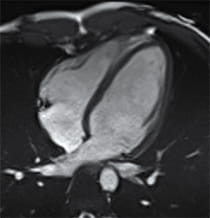

Image of a heart with dilated cardiomyopathy

- MRI of the heart.